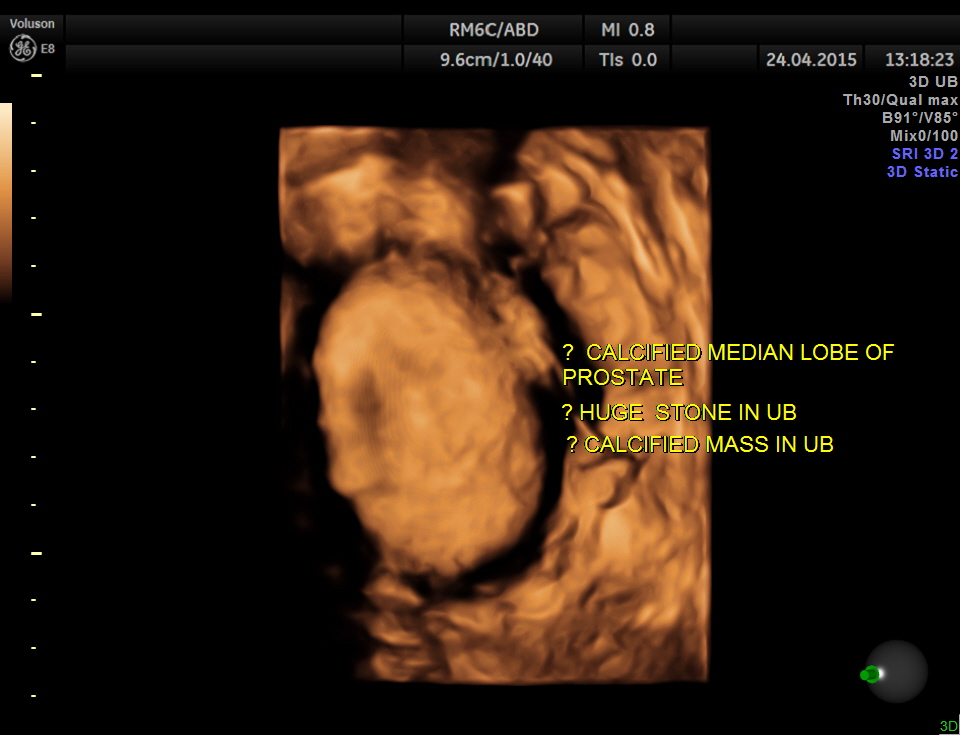

Scan of the urinary bladder in a more cephalic angle shows the following :

A large calcification in the urinary bladder – ? large urinary bladder stone , calcified median lobe of the prostate, or a calcified mass within the bladder .

3D tweaking looks more like a large stone.